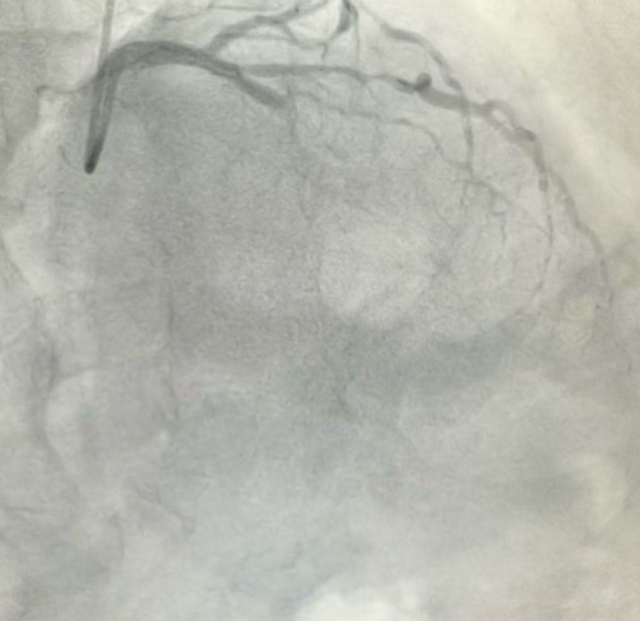

冠脉造影检查显示,于大爷心脏的重要血管——前降支近段完全闭塞,另外两处血管也存在严重狭窄。这意味着心肌供血严重受损,每一分钟延迟都会导致更多心肌细胞坏死。心脏康复科团队迅速为于大爷施行了急诊介入手术,成功在前降支近段植入支架,血流逐渐恢复,胸痛症状随之缓解。